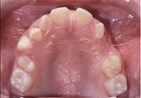

Dental Casts

right buccal frontal left buccal upper mandibular

Right Buccal View Frontal View Left Buccal View Maxillary View Mandibular View